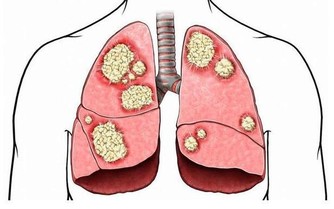

流感是一種由流感病毒(Influenza Virus)引起的呼吸道疾病,主要透過飛沫傳播和接觸傳播。當感染者咳嗽、打噴嚏或說話時,病毒會隨飛沫擴散,而健康的人若吸入這些帶有病毒的飛沫,可能會被感染。因此,口罩的主要作用在於:

- 阻擋飛沫:減少吸入帶有病毒的飛沫。

- 降低傳播風險:防止已感染者將病毒傳播給他人。